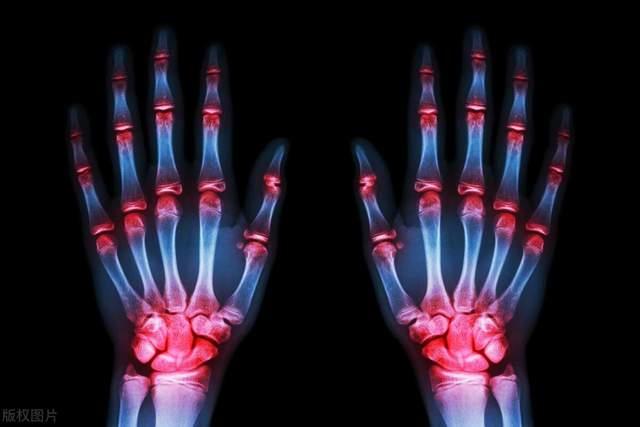

嘌呤是人體內重要的化學物質,存在于許多食物中,也是人體內部一些重要物質(如DNA、RNA)的組成部分。正常情況下,體內的嘌呤會轉化為尿酸并通過腎臟排出。但當體內嘌呤水平過高時最常見的問題就是引發痛風,因為尿酸過多可能會形成晶體沉積在關節或其他組織,引發炎癥和劇烈的疼痛。

尿酸過多還可能形成尿酸結石,導致尿路阻塞和腎臟疼痛。長期的高尿酸血癥會對腎臟造成損害,可能導致腎功能下降